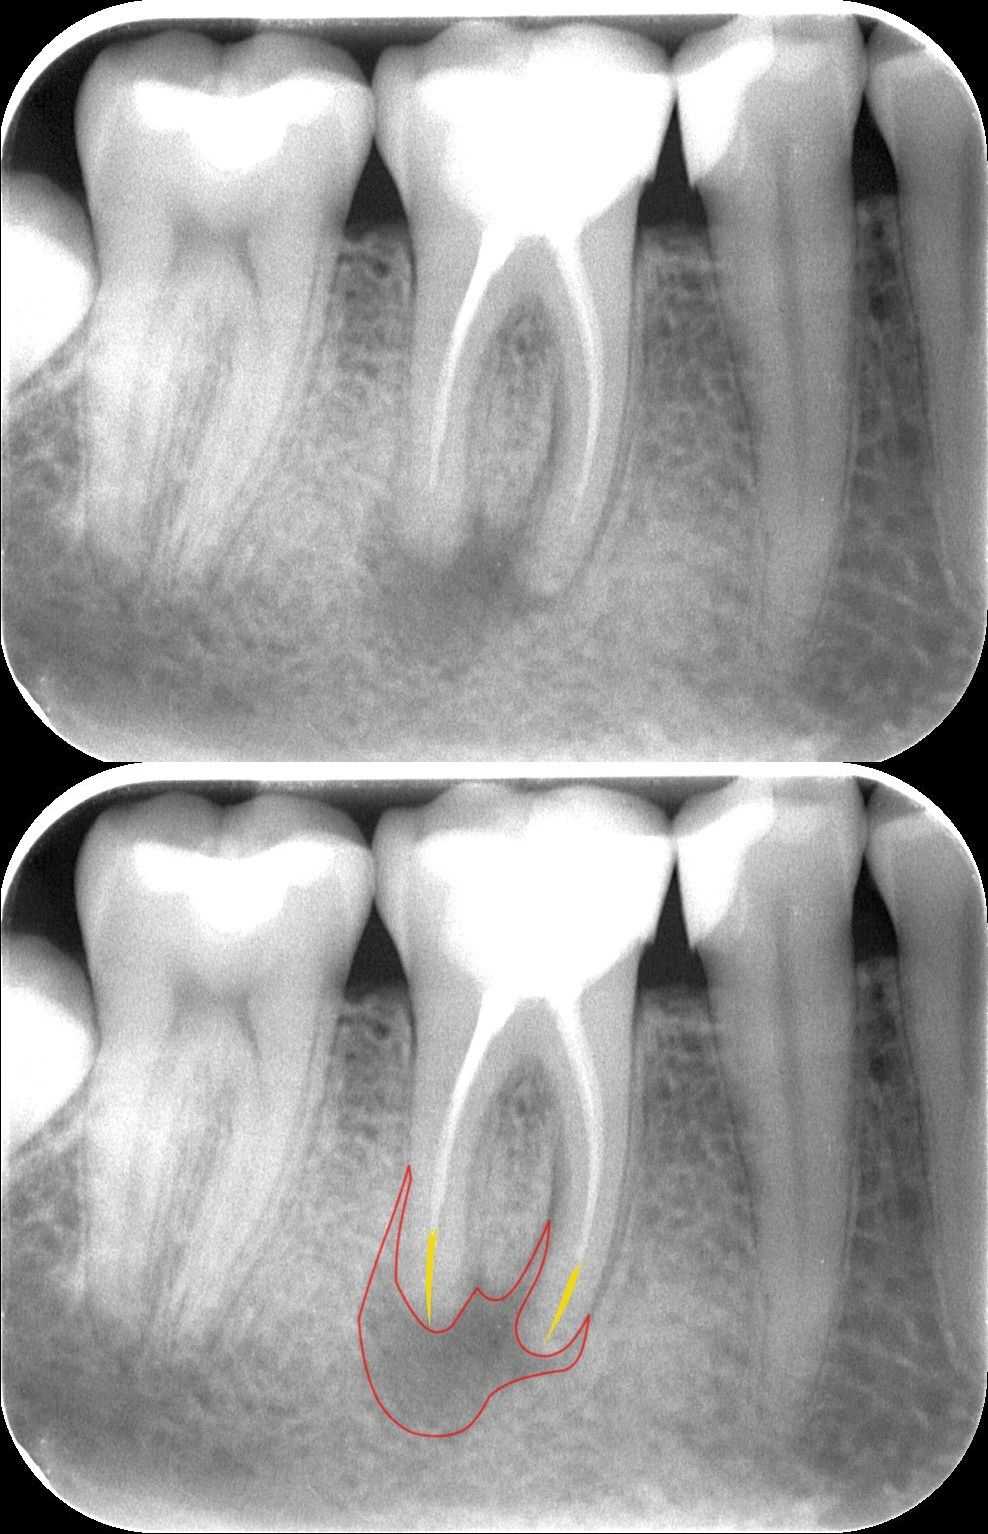

1. A kiinduló röntgenfelvétel

Dr. Kovács Kitti páciense egy három éve készült gyökértöméssel kapcsolatos panaszával kereste fel rendelőnket. A kérdéses fog az utóbbi időben bizonytalan panaszokat produkált. Néha kifejezetten fájt, néha a páciens „érezte”, hogy van foga, néha pedig teljesen panaszmentes volt.

A vizsgálatot egy kisröntgenfelvétel készítésével kezdtük, majd ezt tüzetes szájüregi vizsgálat követte. A fog kopogtatásra érzékeny volt, és a röntgenfelvételen egyértelműen látható lett a csontban lévő krónikus gyulladás (amelyet az alsó képen pirossal rajzoltunk körbe), illetve az ezt kiváltó ok, a rövid gyökértömés (amelynek hiányzó szakaszát sárgával jelöltük).